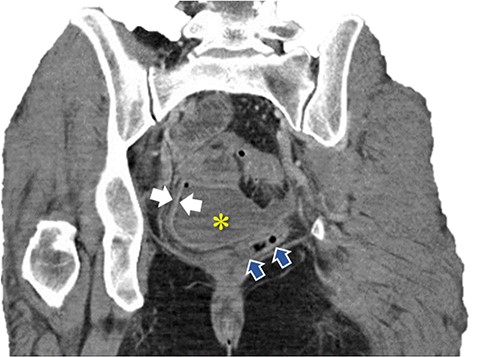

Immediate postoperative course was uneventful until postoperative day (POD)-5 when she experienced multiple watery stools, diffuse abdominal pain, fever (102.6F) and leukocytosis (23000/UL). Clostridium difficile infection was ruled out with a negative stool toxin assay. Her abdominal exam remained nonspecific until POD-6 when she had bilious emesis. A computed tomography (CT) scan revealed perforated diverticulitis with pelvic abscess and multiple colonic diverticulitis with an associated small bowel obstruction (SBO) (Images 1–4). No prior history of diverticulitis was reported.

Coronal image of pelvic abscess cavity. *: pelvic abscess cavity; White arrows: rim-enhancing pelvic abscess cavity; Blue arrows: collapsed sigmoid colon with multiple diverticuli.